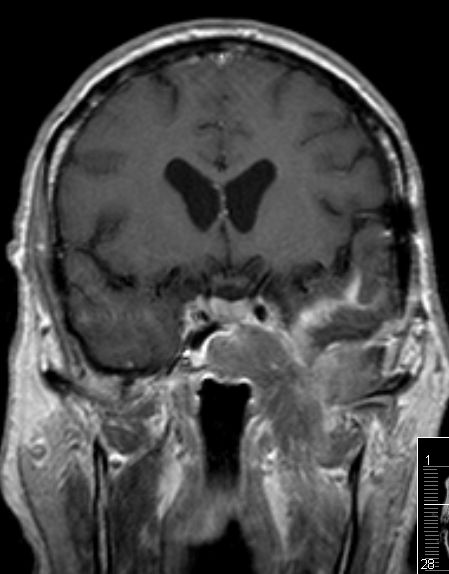

| Fall | Im vorliegenden Fall kam es während der Temodal-Therapie nach postoperativer Radiochemotherapie zu einen Durchbruch des GBs durch die Schädelbasis. | |